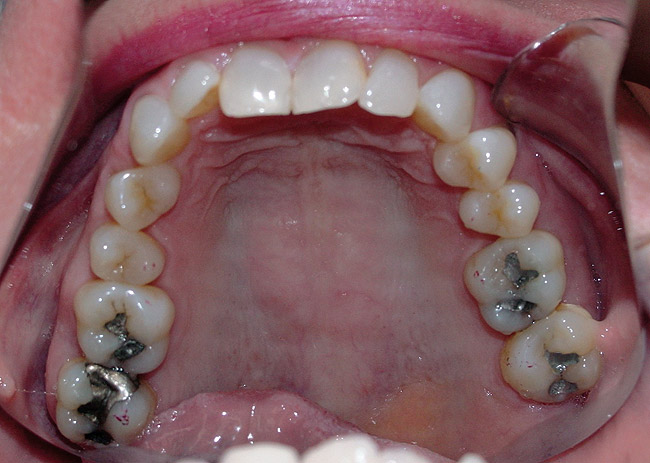

Figure 9  The mandibular posterior teeth are at  a lower vertical height than the anteriors, creating  a deep bite and a concomitant posterior  shift. The tongue fills in the space at rest.

Figure 9